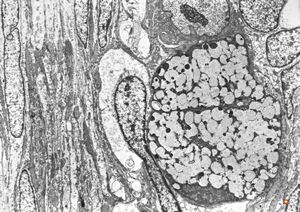

F,31y. | ovary - mucinous carcinoma